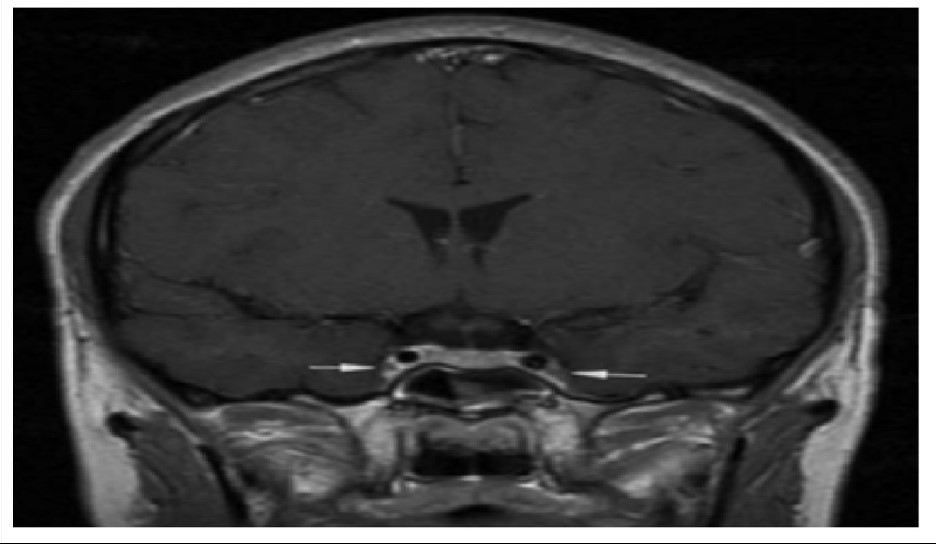

Theo hồ sơ bệnh án, bệnh nhân khởi phát bằng viêm xoang cấp mủ, sau đó chuyển sang viêm tấy nửa mặt, rồi nhanh chóng xuất hiện rối loạn ý thức và co giật. Kết quả chụp cộng hưởng từ sọ não cho thấy: Phù nề lan tỏa, dấu hiệu điển hình của viêm tắc tĩnh mạch xoang hang - một tình trạng huyết khối nhiễm trùng ở nền sọ.

Vị trí mũi tên là viêm và co thắt động mạch cảnh trong 2 bên